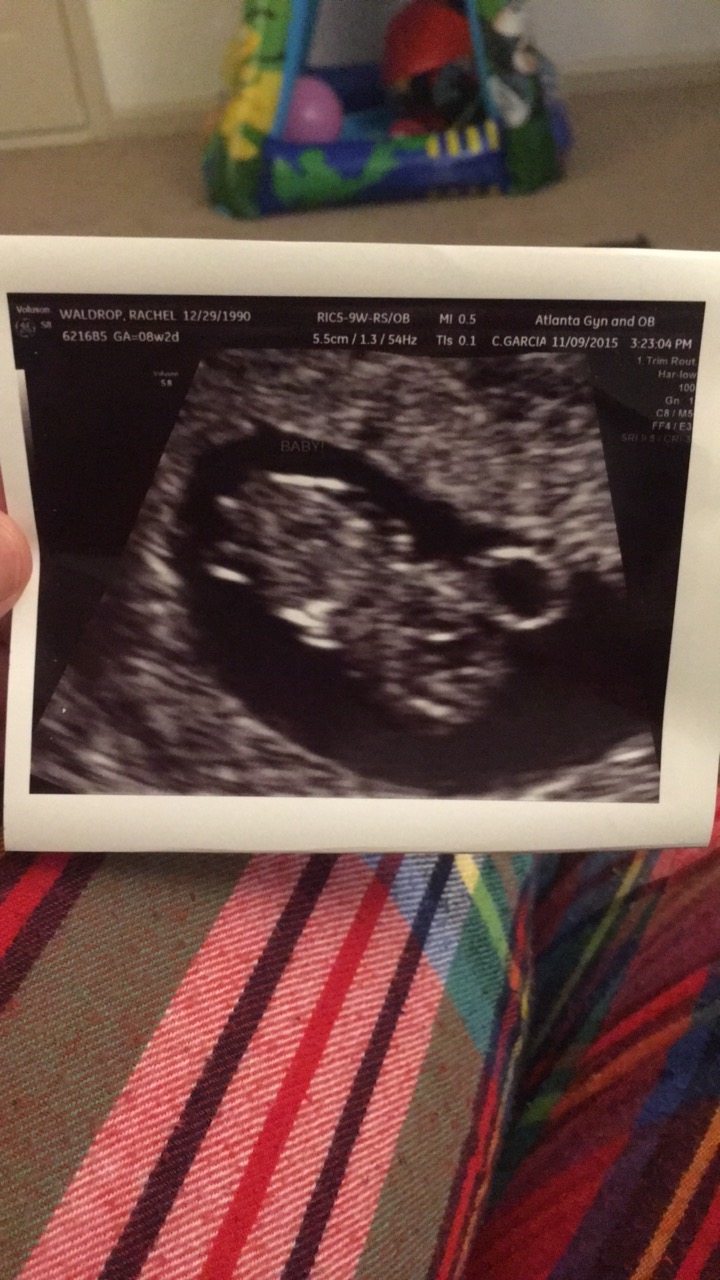

Had our first scan today at 9w5d HB 178!! My OB had trouble with the machine so the measurement is a little smaller than what baby really is, going for NT scan in a few weeks